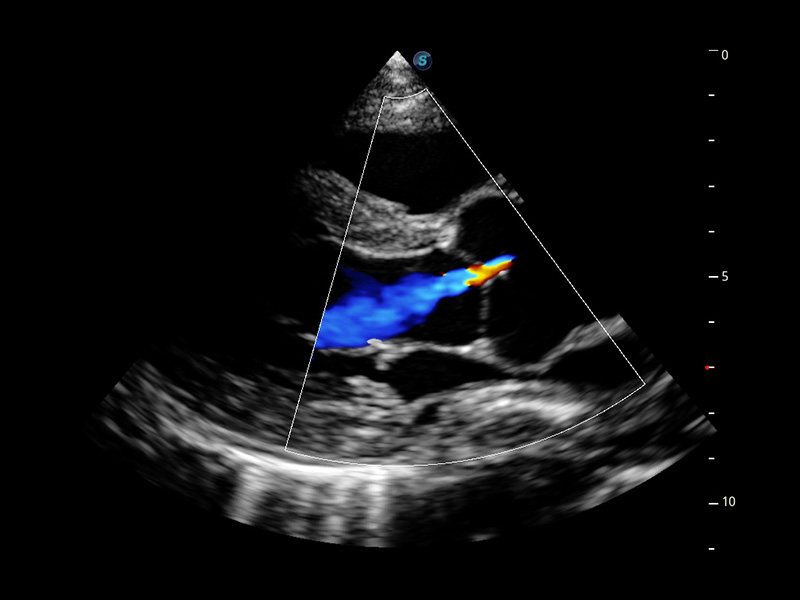

Cardiovascolare avanzato

Si impegna a fornire una soluzione completa per la valutazione cardiaca

Dotato dell'esclusivo trasduttore a cristallo singolo SonoScape e di una tecnologia di elaborazione all'avanguardia, P60 si impegna a ripristinare ogni dettaglio ed elemento per una diagnosi precisa. La nuova analisi quantitativa del miocardio (MQA) fornisce un referto quantitativo approfondito sulle dinamiche del movimento della parete miocardica globale e regionale del ventricolo sinistro, offrendo ai medici una valutazione completa delle funzioni miocardiche.

• Stress Echo

• MQA con analisi della deformazione

• TDI (Tissue Doppler Imaging)

• Opacizzazione VS

• Auto EF